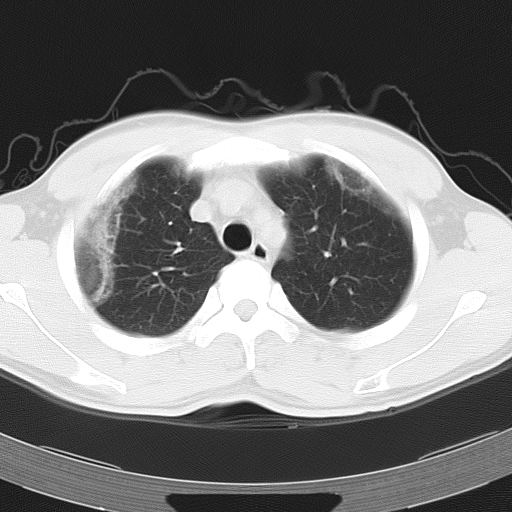

标题: CT12379:男,34岁,肺部病变,请求会诊!

男,34岁,咳嗽2~3个月,无咳血,病初有发热。

两上肺磨玻璃样改变,均位于肺外周,考虑1、肺泡蛋白沉着症?2、肺泡炎?请询问有无养鸟史 3、脱屑性间质性肺炎?建议进一步检查、复查随访

两上肺的ggo,靠近胸膜,不是以节段分布,青年男性,个人意见为吸入性的真菌感染可能为大------------呼吸内科医生

两肺上叶近胸膜磨玻璃样阴影,考虑1、炎性病变。 。2、过敏性炎症?

病灶特点:

分布在肺野的外带,病灶边缘清楚,病灶以磨玻璃影为主夹杂少许纤维状高密度影

支持zhangzhongshou主任,考虑蛋白沉着症可能性大

再仔细阅读该病人的ct片,我们不难发现,病例所表现的正是外围型的肺泡蛋白沉积症表现,即:为多发性条片状、斑片状及斑块状高密度影,弥散、对称或不对称分布于两肺或一侧肺外围部位。病变区与正常肺组织及脏层胸膜面分界清晰,呈地图样改变。